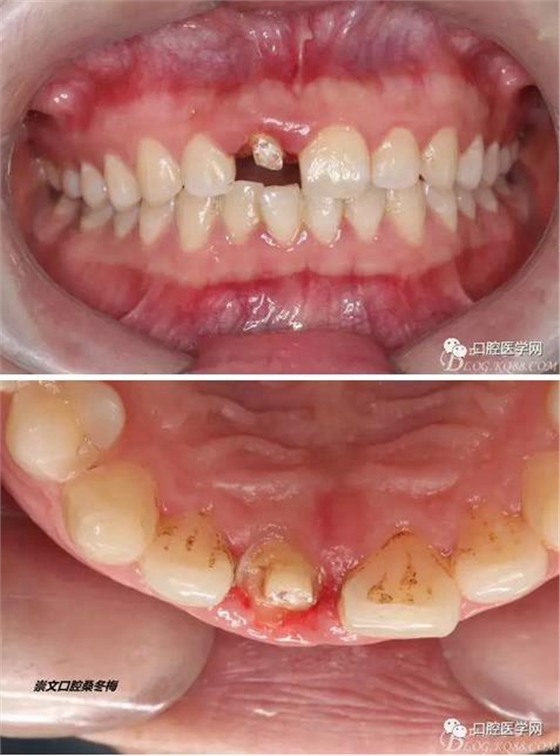

術(shù)前口內(nèi)照,11殘根,唇側(cè)牙齦紅腫,肩臺在齦下2毫米,舌側(cè)正常.21有被動萌出,長寬比例不協(xié)調(diào)??谇恍l(wèi)生一般,有菌斑。

術(shù)前原有牙冠復(fù)位,牙齦紅腫。